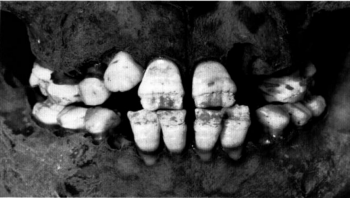

DEH

Dental enamel hypoplasia (DEH) is a condition characterised by fluctuating growth in the dentition. The pathology can be identified macroscopically by lines, pits, and grooves in the dental enamel (figure 2), reflecting reduced mineralisation during childhood (Hillson 2005, 168). DEH does not have a specific aetiology and is considered a non-specific indicator of early childhood stress.